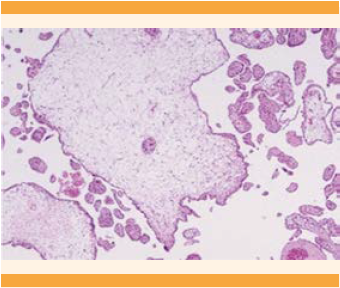

Durante las primeras 48 horas tuvo sangrado transvaginal profuso (mayor de 200 mL, de color rojo rutilante, no doloroso); no se registraron datos de gasto cardiaco, pero se observó pérdida del bienestar fetal (bradicardia de 100 lpm mediante registro electrocardiotocográfico), por lo que se decidió la interrupción del embarazo por cesárea de urgencia. Puesto que se trataba de un embarazo con alta morbilidad y mortalidad, y la paciente tenía paridad satisfecha, se decidió realizar cesárea-histerectomía con la técnica de Esperanza-Bautista (Figura 3). Se obtuvo un recién nacido femenino, con peso de 1416 g, Capurro de 3 semanas y APGAR 7/9. Los hallazgos más sobresalientes fueron: placenta previa total, con proliferación anormal del trofoblasto, vesículas y edema velloso (Figura 4). No se registraron incidentes ni complicaciones pre ni posoperatorias. Se estimó un sangrado de 700 mL. Durante el seguimiento, 72 horas después de la cesárea, la concentración de la fracción β-hCG fue de 16,549 mUI/mL y después de una semana de 3,984 mUI/mL. Por el momento la paciente permanece en seguimiento semanal; cuando cumpla tres semanas consecutivas con resultado negativo continuará la determinación de β-hCG cada dos semanas por dos meses y, finalmente, de manera mensual durante un año. El reporte de patología fue proliferación anormal del trofoblasto, vesículas y vellosidades hidrópicas (Figura 5).